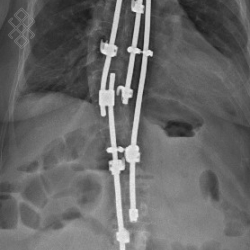

TéléRadiographie du Rachis en totalité

La durée de l'examen est d'environ 5 minutes. Un ou plusieurs clichés radiographiques seront effectués. Le manipulateur vous positionnera en fonction de l'incidence radiologique à réaliser. Sauf indication contraire, il sera important de ne pas bouger durant la prise de clichés.